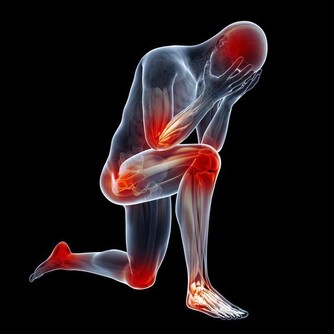

糖尿病足:高血糖導致下肢血管、神經系統病變,一旦皮膚稍有破損、感染而不及時感知或治療,將會迅速形成潰瘍、壞疽,最終不得不做截肢處理,造成病人身體上、心理上雙重打擊,生活質量大大下降,嚴重的甚至還會危及生命。